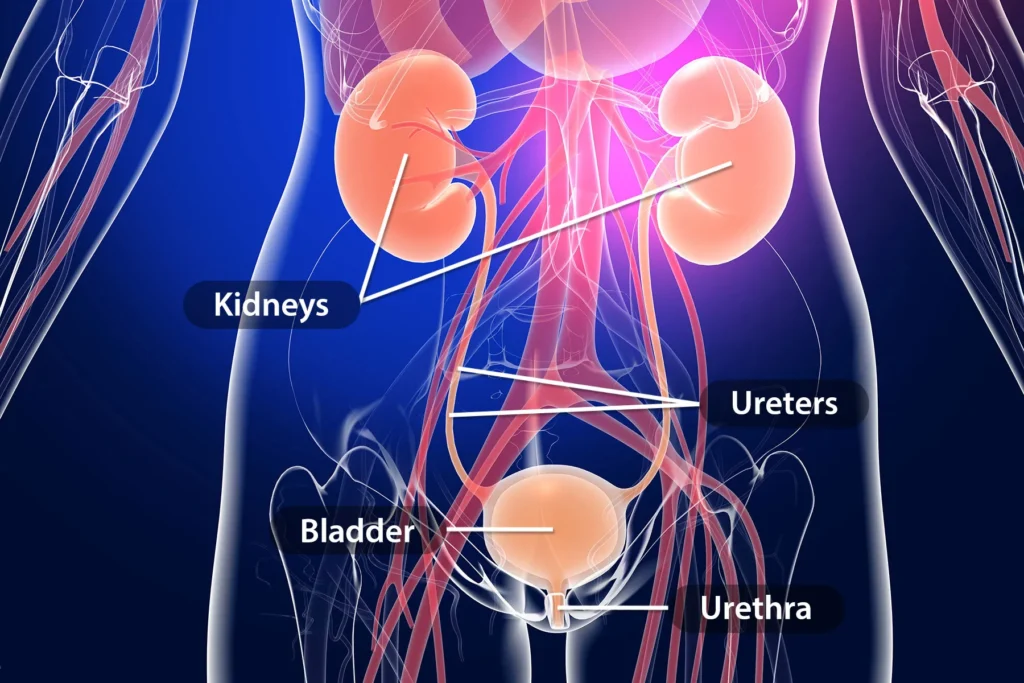

Urinary Tract Infections (UTI)

UTIs occur when bacteria enter the bladder or kidneys. While common, frequent infections in children can signal structural issues like Reflux (VUR). Prompt treatment is necessary to prevent scarring of the delicate growing kidneys.

Approach

- Urine Culture Test

- Renal Ultrasound

- MCUG/DMSA Scans

- Hygiene Education